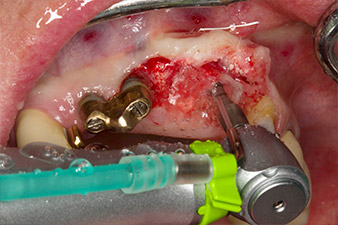

След първичното оздравяване, меките тъкани са оформени посредством базално разположения мост. Два месеца по-късно, обработваното поле е изложено на палатинална алвеоларна инцизия (Фиг 2). Размерите на алвеоларната кост са достатъчни в позиция 22. Фигури 2 и 4 показват препарацията на имплантното ложе, нарязващия винт и имплатирането, използвайки Implantmed.

С цел да се компенсира периодонталната загуба на кост и да се постигне естетически добър резултат, имплантирането е комбинирано с водена костна регенерация (GBR) с ксеногенен заместващ материал и колагенова мембрана (Фиг. 5 и 6).